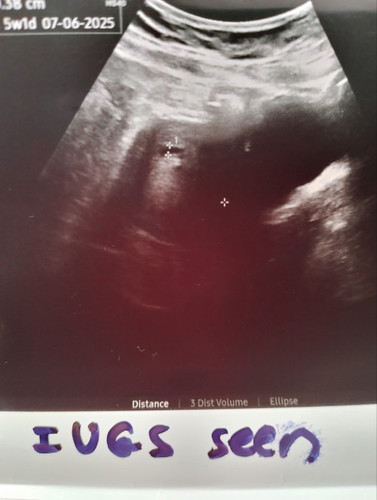

Tadi sy p scan.. nampk kantung dan kata doc kantung bru 5w1ari.. tp ikut kiraan period sy dah 8w harini..mmg period sy selalu delay 2,3,4 hari pun.. risau sy sebenarnya takut sejarah lalu berulang kembali.. gugur.. doakan sy ng bby sihat je kawan2..lagi 3minggu repeat scan at klinik swasta

sama dgn sy 8w ari ni.. tp smlm g scan nmpk kantung je 6w 4d..lg 2 mggu scan lg